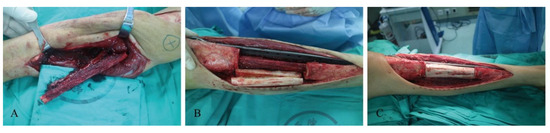

3.1. Upper Extremity Reconstruction Results

| 1 | 120 | 140 | No | devitalized autograft, single plate | 150 | 600 | 51 | 3 | 30 | / |

| 2 | 85 | 110 | No | allograft, single plate | 150 | 500 | 62 | 5 | 29 | / |

| 3 | 70 | 100 | No | allograft, single plate | 150 | 400 | 96 | 3 | 30 | / |

| 4 | 90 | 120 | Yes | devitalized autograft, single plate | 105 | 500 | 37 | / | 21 | Infection, Nonunion |

| 5 | 100 | 130 | No | allograft, single plate | 180 | 500 | 57 | 7 | 28 | / |

| 6 | 90 | 120 | No | devitalized autograft, single plate | 280 | 850 | 83 | 6 | 30 | / |

| 7 | 75 | 110 | No | devitalized autograft, single plate | 120 | 500 | 74 | 3 | 30 | / |

| 8 | 85 | 110 | No | devitalized autograft, single plate | 150 | 500 | 66 | 5 | 27 | / |